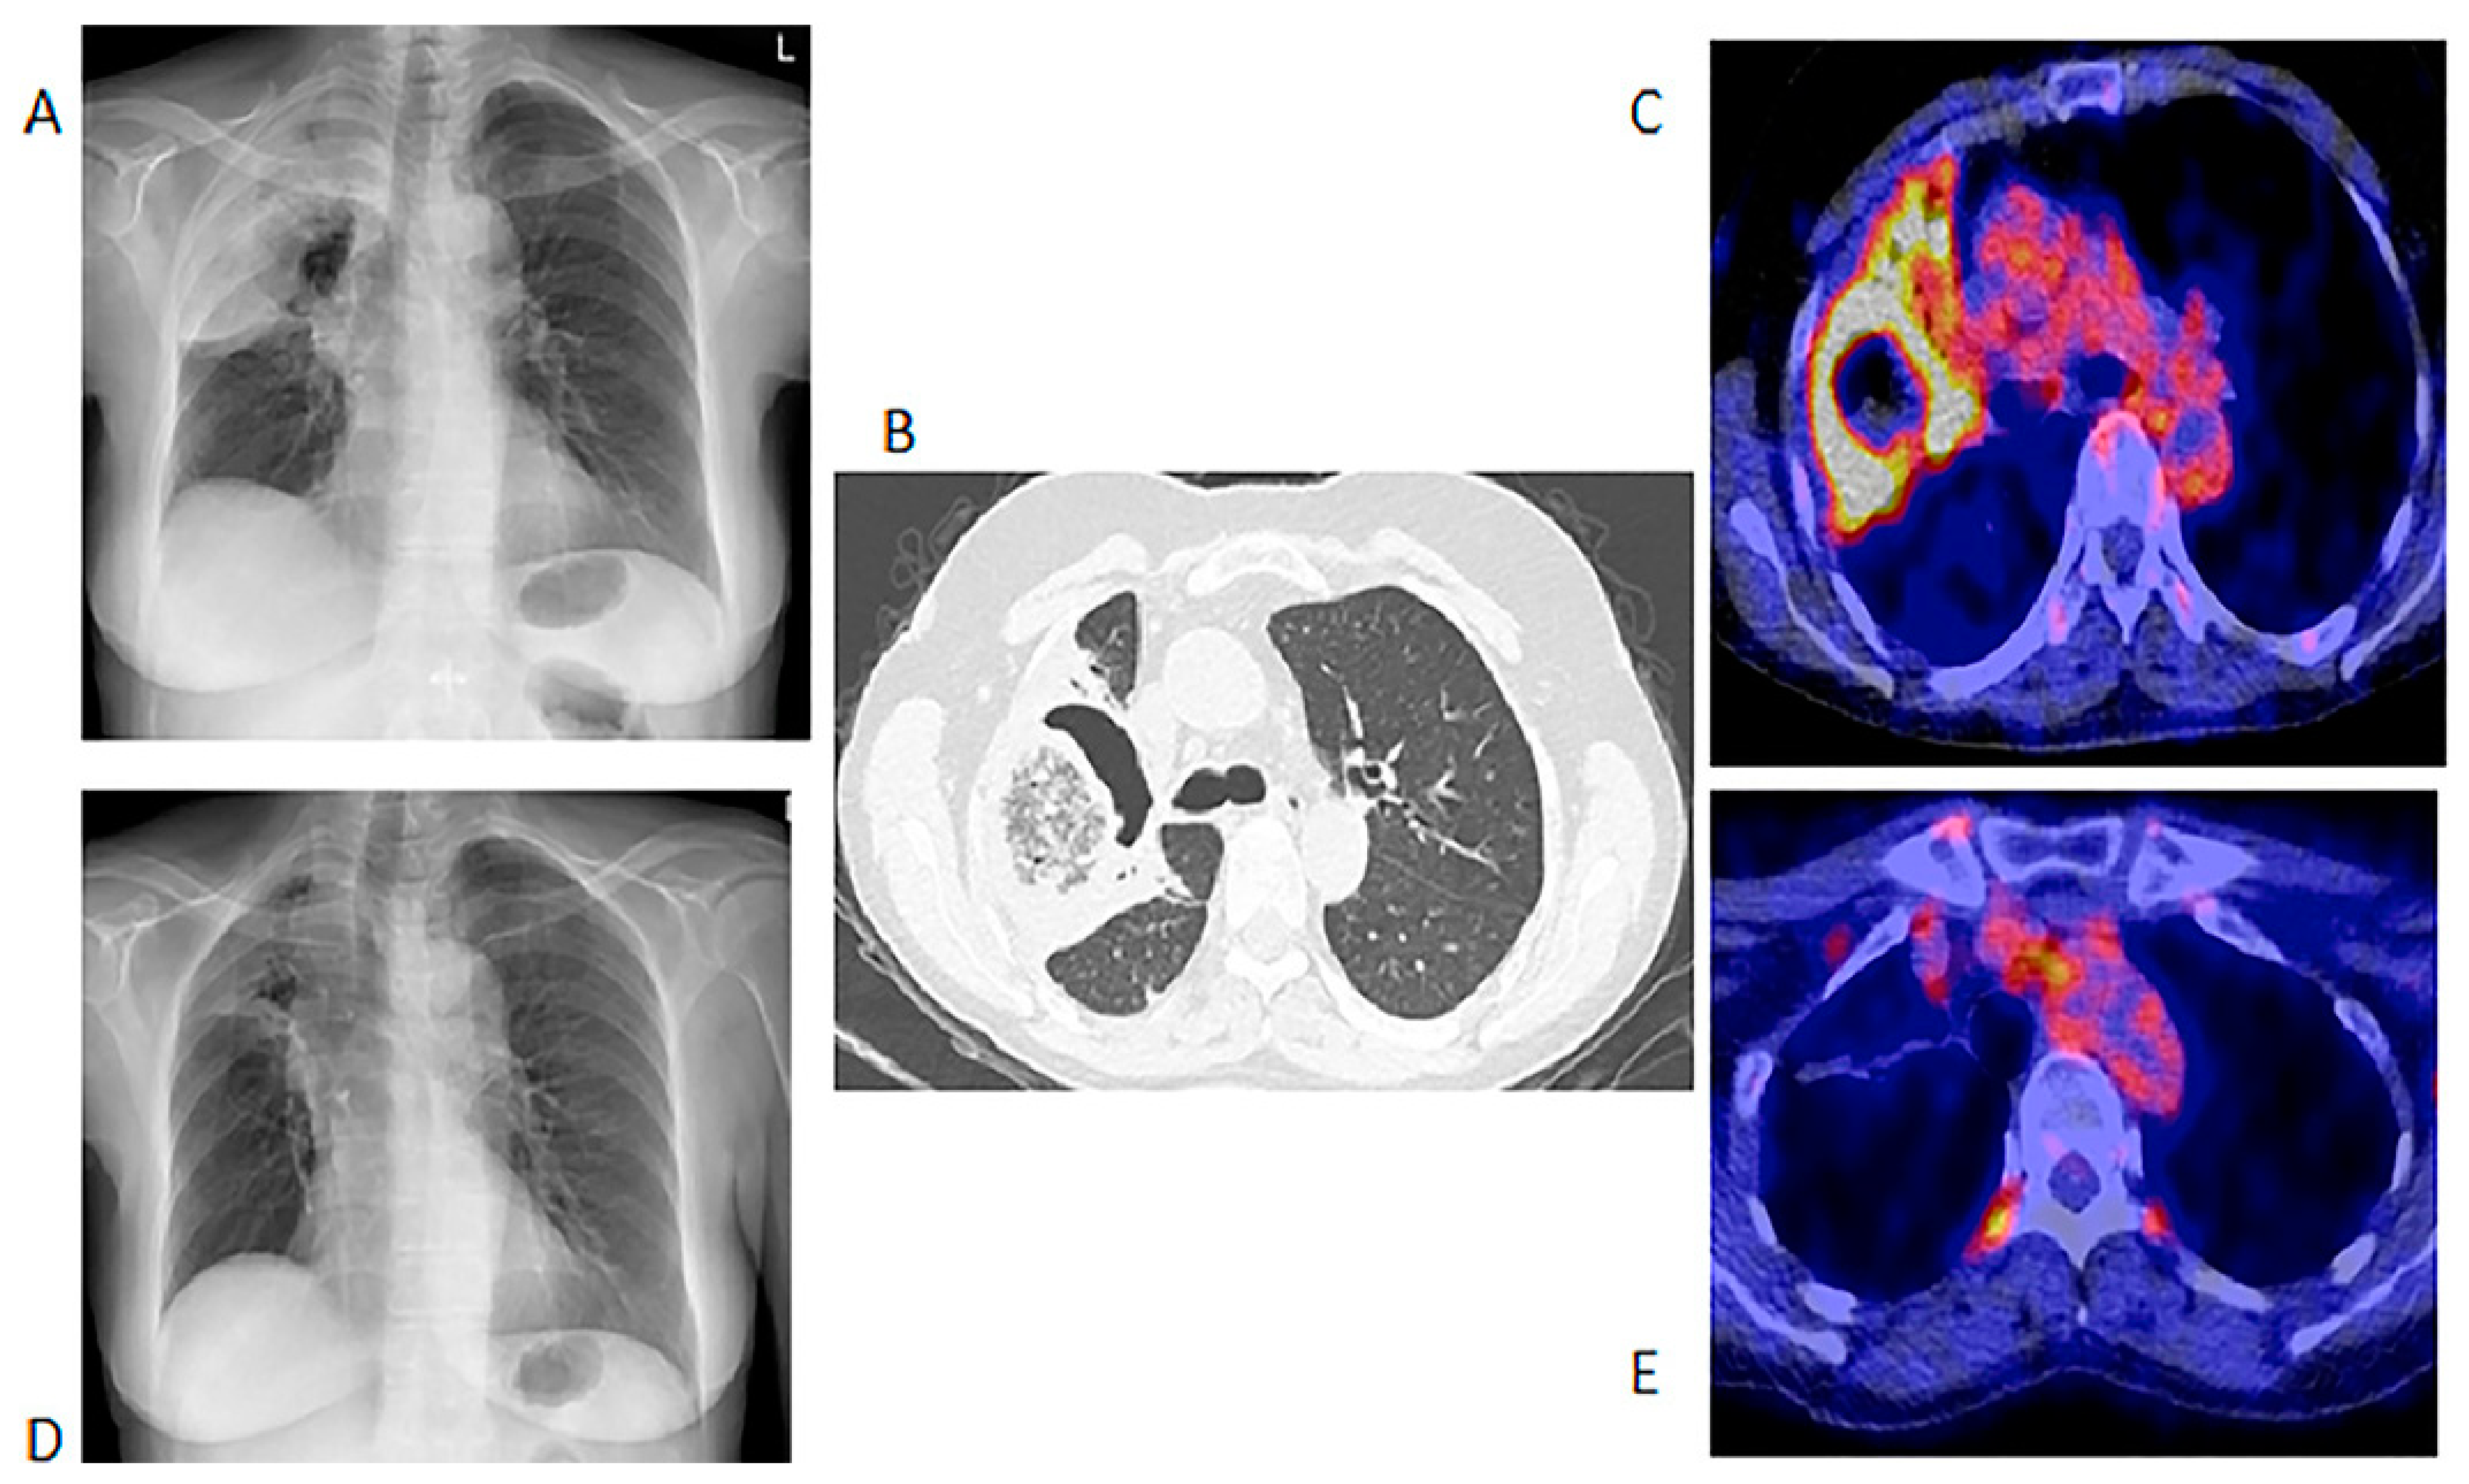

We included 155 [18F]FDG PET/CT studies from 73 patients who were diagnosed with IFIs. The majority of the patients (n = 49, 67%) were males, and the median age at the time of the scan was 56 years, with a range from 9 months to 76 years. Fifty-nine (81%) patients were from UMCG, and fourteen (19%) were from UMCU. Forty-one patients had a single [18F]FDG PET/CT in the assessment of IFIs. The IFIs were classified according to the revised EORTC/MSG criteria, and the results are displayed in Table 1. Thirty-two patients had repeated [18F]FDG PET/CT studies performed to monitor the responses (Table 2). Fourteen (45.1%) of the patients who had repeated [18F]FDG-PET to monitor the treatment of the IFIs did not have proven IFIs as per the EORTC/MSG criteria. The conditions underlying the IFIs are tabulated in Table 1. There were five major indications for [18F]FDG PET/CT study. These five indications are displayed in Table 2 below. Figure 1 shows the initial chest X-ray, HR CT and fused axial [18F] FDG PET/CT through the chest of a patient with a proven fungal infection and the follow up [18F]FDG PET/CT study.

Figure 1.

Chest X-ray, HR CT and [18F]FDG PET/CT of a 60-year-old female with acute myeloid leukemia on chemotherapy. She had a proven fungal infection (Alternaria alternata). (A)—Initial chest X-ray. (B)—Initial HR CT scan performed before the [18F]FDG PET/CT. (C)—Fused axial image of [18F]FDG PET/CT of the chest. After 2 months of antifungal therapy. (D)—Chest X-ray showing response with a residual lesion. (E)—Fused axial [18F]FDG PET/CT showing an almost complete metabolic response in the IFI lesion. The data provided by [18F]FDG PET/CT at follow-up were deemed adequate, so patient did not require a repeat HR CT.